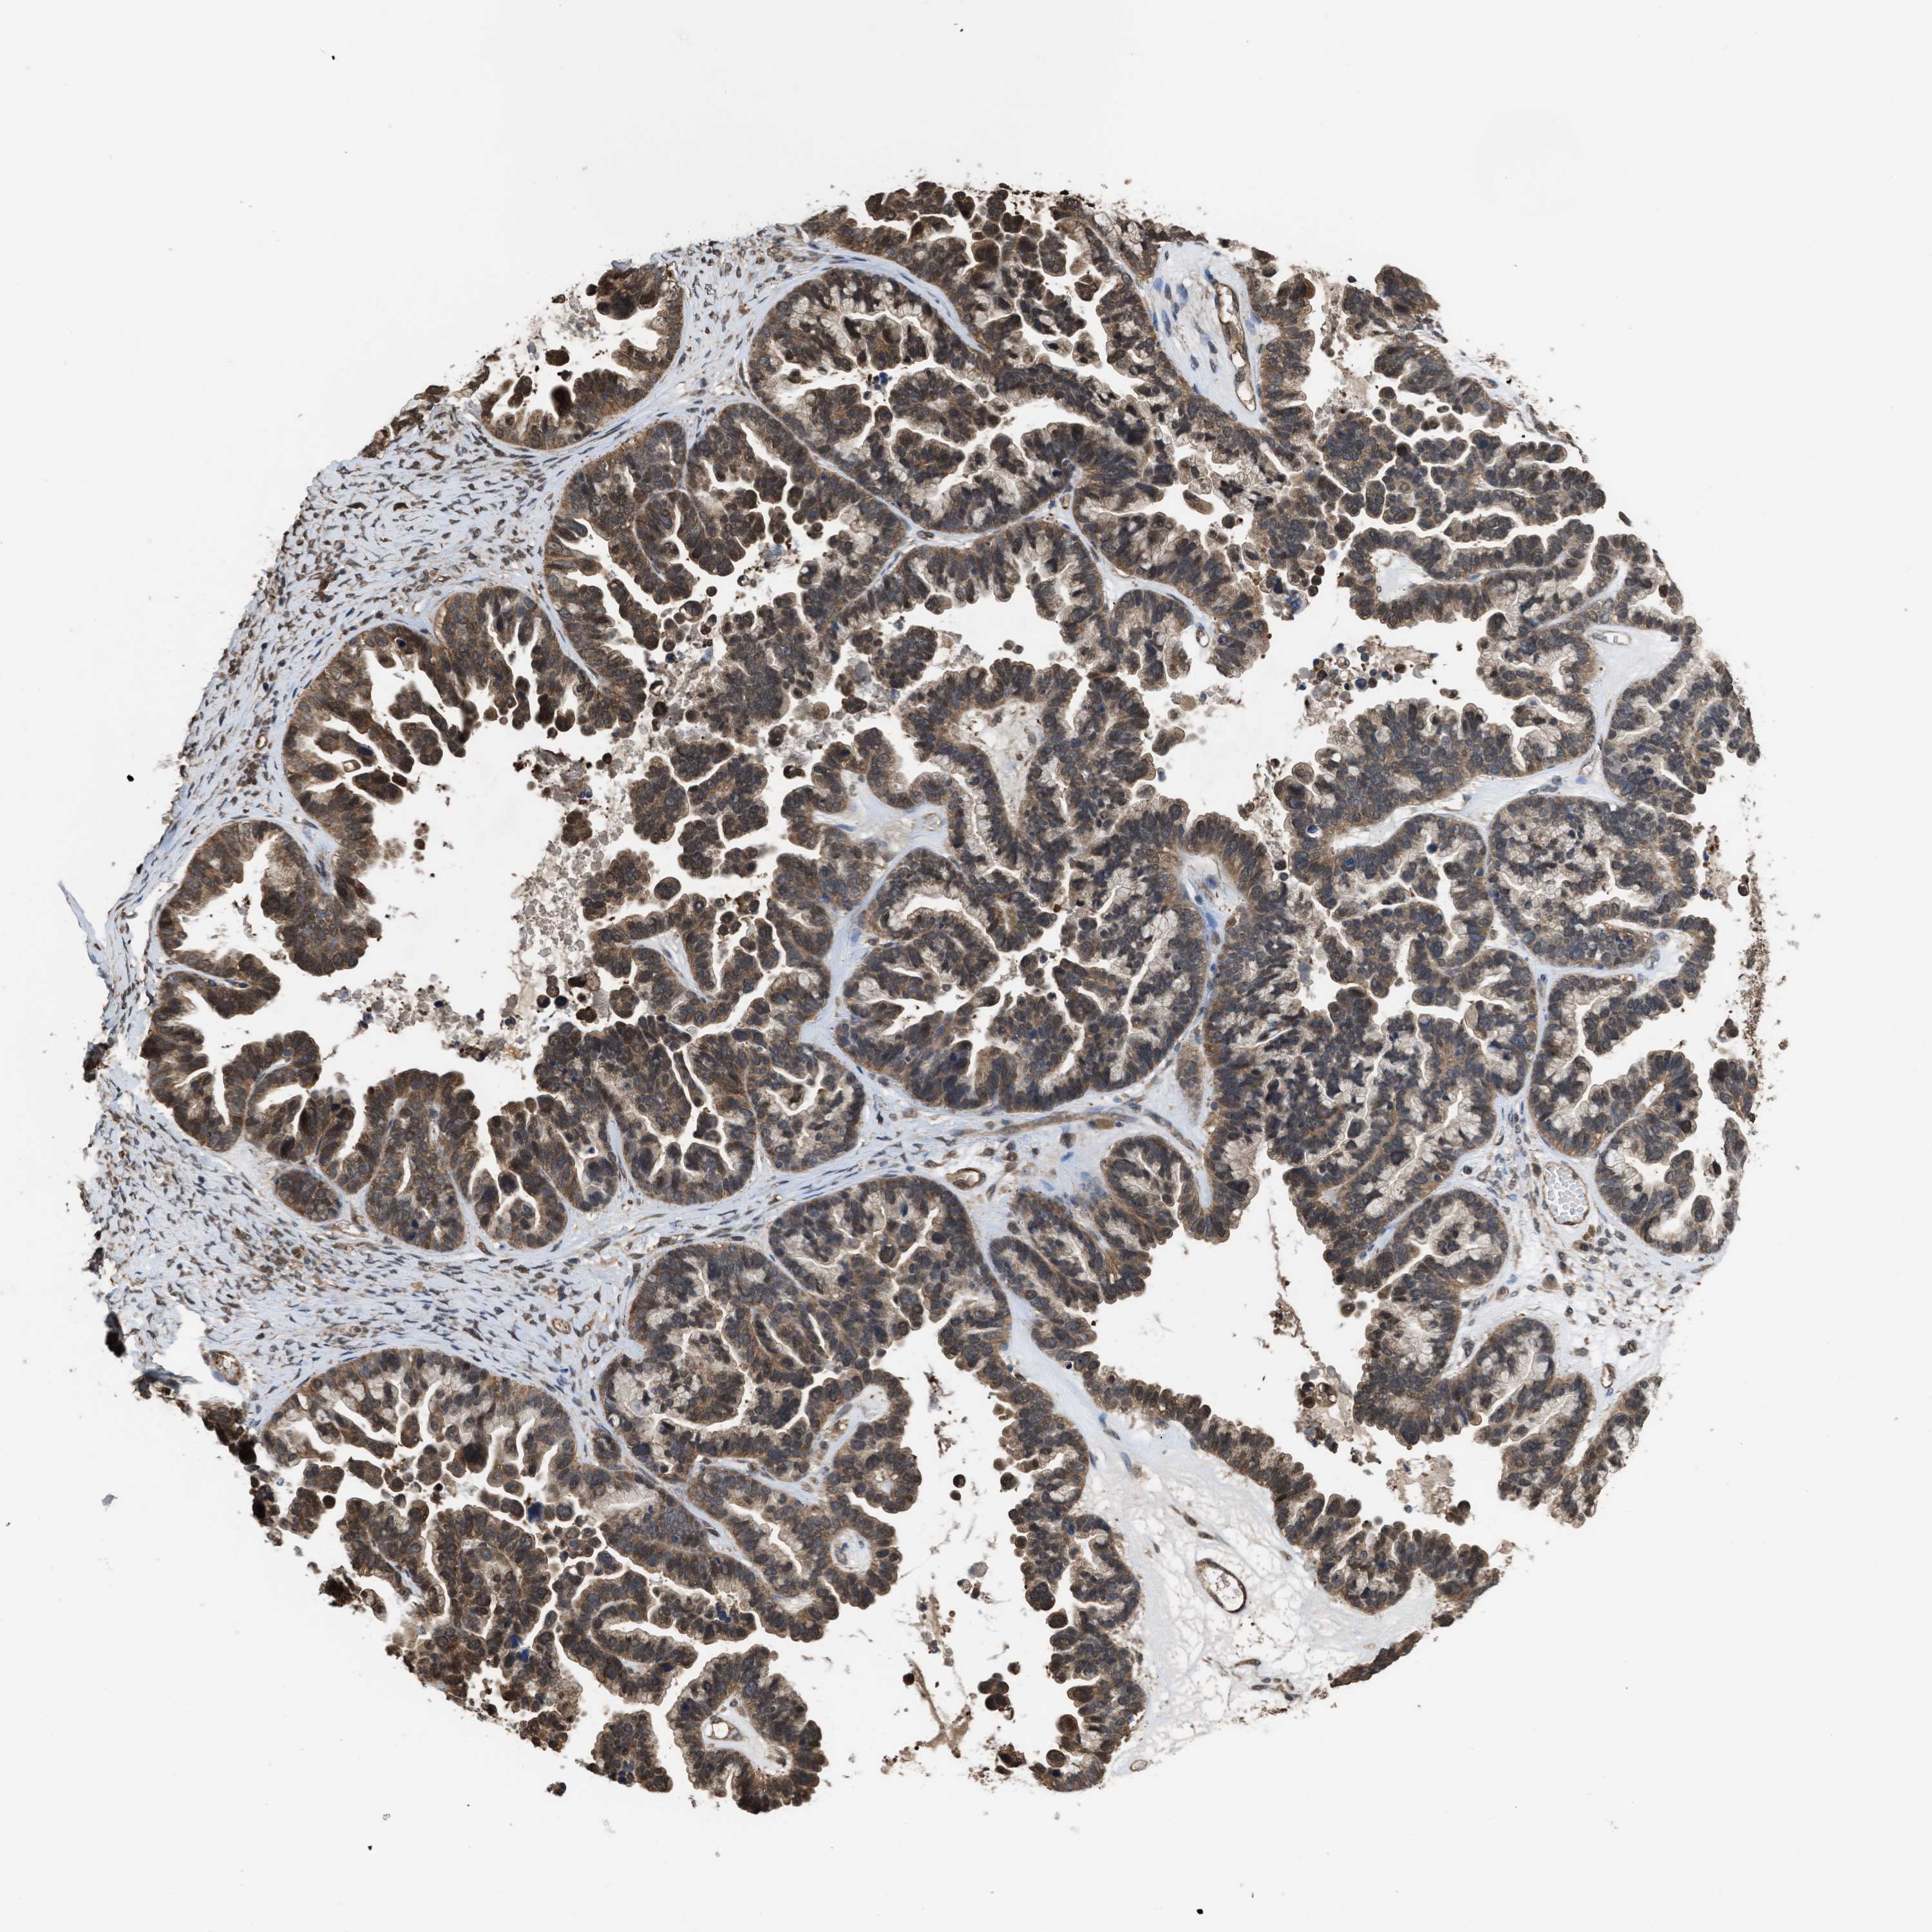

OVARIAN CANCER - Protein expressioni

A mouse-over function shows sample information and annotation data. Click on an image to view it in a full screen mode. Samples can be filtered based on level of antibody staining by selecting one or several of the following categories: high, medium, low and not detected. The assay and annotation is described here.

Note that samples used for immunohistochemistry by the Human Protein Atlas do not correspond to samples in the TCGA dataset.

Antibody stainingi

Antibody staining in the annotated cell types in the current human tissue is reported as not detected, low, medium, or high, based on conventional immunohistochemistry profiling in selected tissues. This score is based on the combination of the staining intensity and fraction of stained cells.

Each image is clickable and will lead to virtual microscopy that enables deeper exploration of all samples and also displays staining intensity scores, fraction scores and subcellular localization as well as patient and tissue information for each sample.

Antibody HPA026918

Antibody CAB013274

Antibody CAB018389

Staining

High

Medium

Low

Not detected

Cystadenocarcinoma, serous, NOS